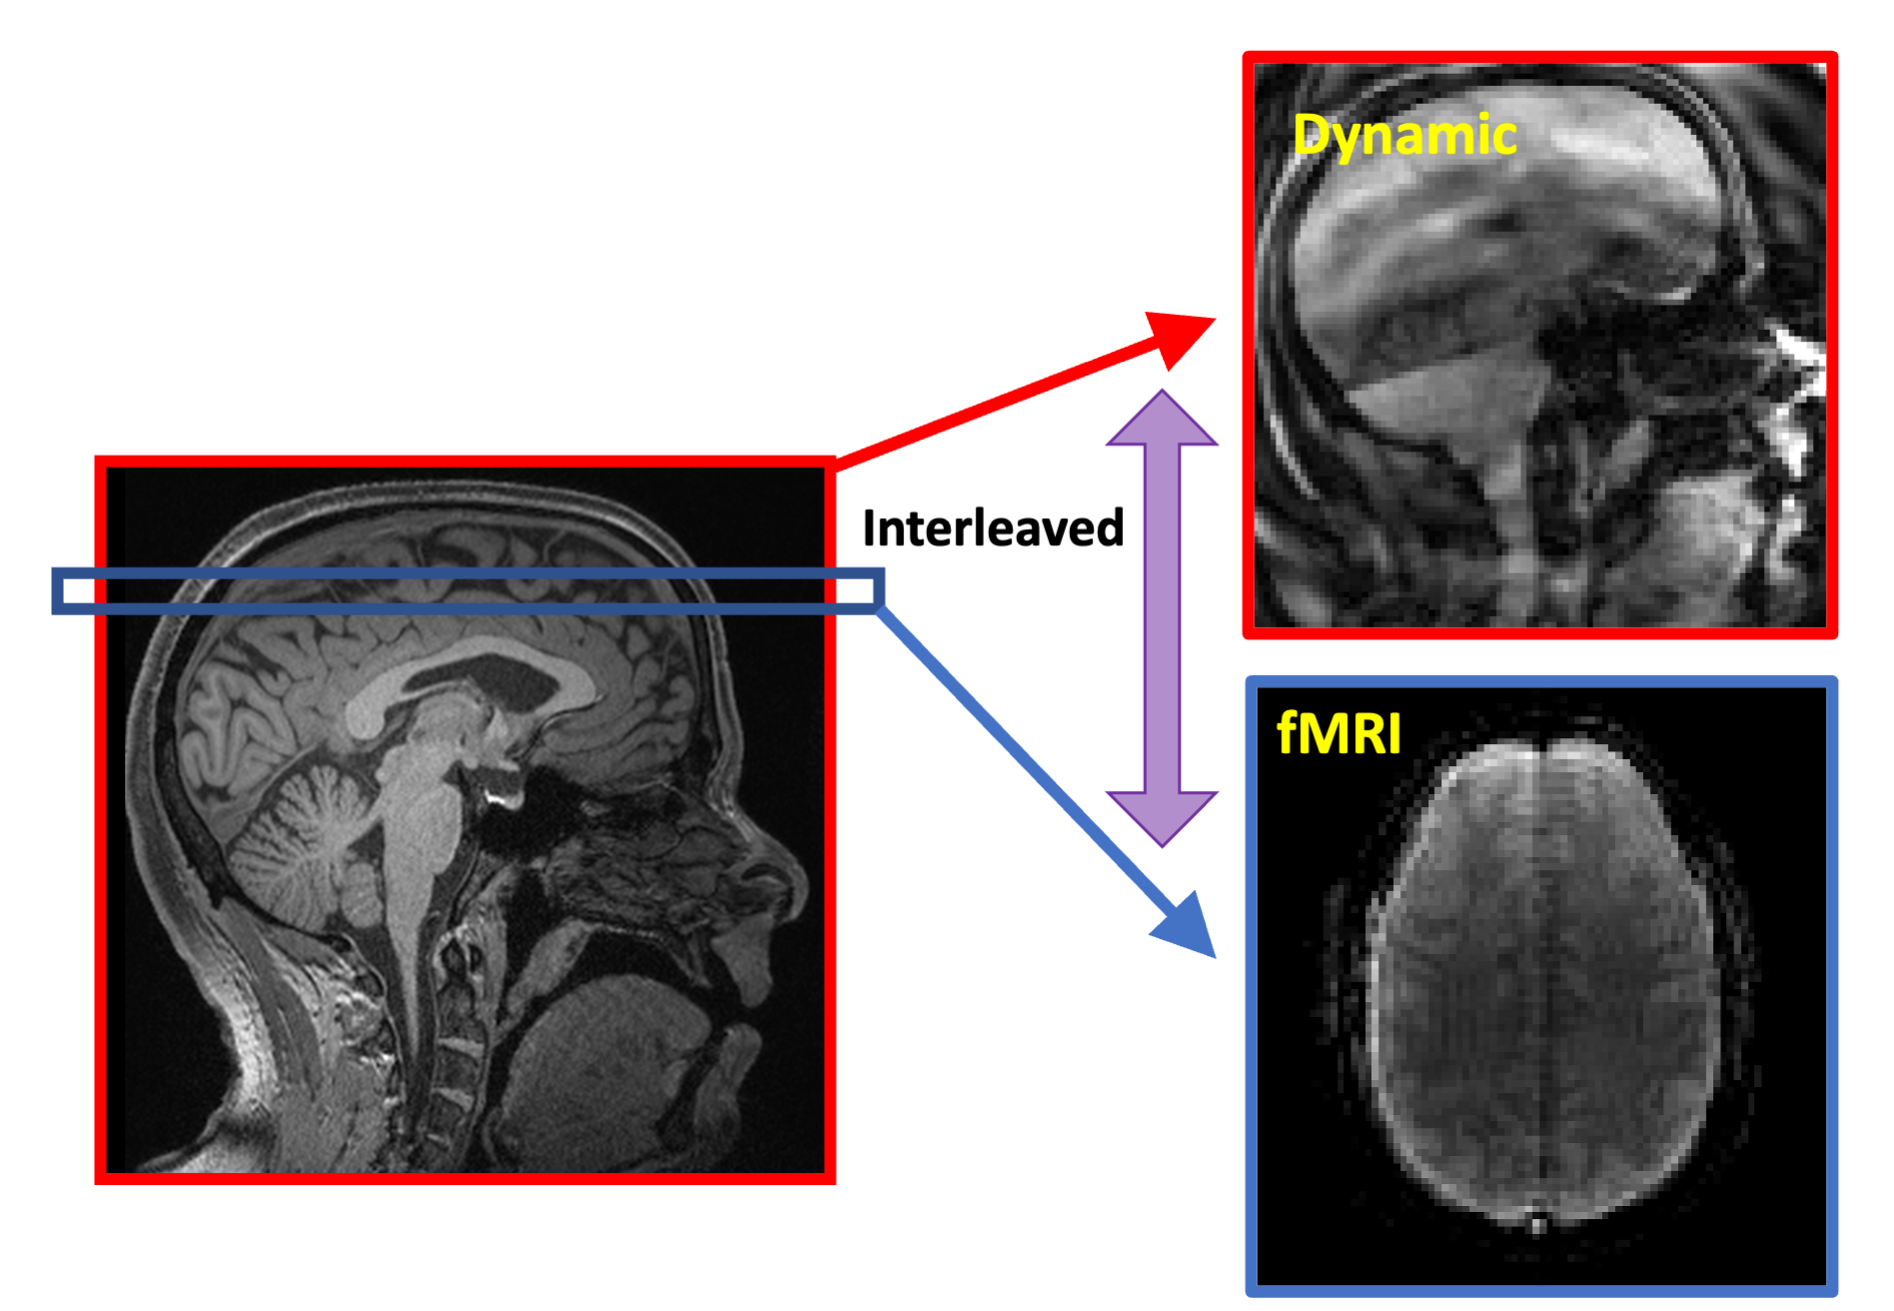

Figure 1: Gradient waveform for the x-axis, showing the navigator acquisition of a spiral in, followed by multi-shot spiral out imaging gradients. For each dynamic acquisition, a navigator is acquired along with 1 shot of imaging k-space.

The Partial Separability (PS) model acquires a temporal navigator at each time point and then only one shot of the imaging data that highly undersamples (k, t)-space. After the temporal basis is determined from the temporal navigators with very high temporal resolution, the corresponding spatial basis of the PS model can be determined from the sparsely sampled imaging data across the time series. For this work, we designed a navigator that was one shot of a 24-shot, 64-matrix size spiral-in navigator. This was immediately followed by acquiring one shot of a 24-shot, 128-matrix size spiral-out imaging data. The navigator and imaging readouts were concatenated together as shown in Figure 1. SimulScan proceeds by acquiring one of these dynamic shots in between each 2D functional MRI slice (see Figure 2). The fMRI was a spiral-in, TE = 25 ms, 96 matrix size trajectory with a reduction factor of 2, reconstructed by SENSE5,6. We used a 38-slice fMRI acquisition with 3 mm slice thickness, fat sat on, resulting in an overall TR (fMRI slice and dynamic shot) of 76.6 ms, 13 fps dynamic imaging, and an overall TR for 38 slice fMRI data of 2.9 s. A healthy adult subject was scanned for 9.5 minutes and asked to tap their tongue several times during the course of the run, without cue and at their own pace, trying to get at least 20 taps in the run.